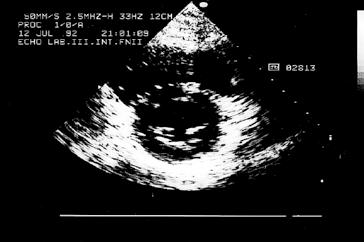

Kromě nakladatelství a výtvarníka se o definitivní podobu třetího dílu učebnice zasloužili mnozí odborníci. Za poskytnutí rtg snímků jsem již od vzniku 1. vydání 3. dílu učebnice vděčný Radiodiagnostické klinice 1. LF UK a paní doc. MUDr. Běle Drugové, DrSc., z radiodiagnostického oddělení Nemocnice Na Homolce. Za vynikající mikrofotografie z vývoje oka děkuji panu prof. MUDr. Františku Vrabcovi, DrSc., který mi je poskytl pro tuto knihu. Panu prof. MUDr. Oldřichu Eliškovi, DrSc., a paní doc. MUDr. Miloslavě Eliškové, CSc., děkuji za poskytnutí podkladů z jejich studií pro vytvoření obrazů mízního odtoku ze srdce. Panu doc. MUDr. Jaromíru Hradcovi, CSc., ze III. interní kliniky 1. LF UK děkuji za poskytnutí echokardiografických obrazů srdce. Upřímně děkuji též oběma spolupracovníkům, panu prof. MUDr. Rastislavu Drugovi, DrSc., a panu prof. MUDr. Miloši Grimovi, DrSc., za porozumění a sympatickou spolupráci na tomto vydání knihy. Studentům, učitelům anatomie i lékařům přeji, aby jim kniha sloužila jako užitečný průvodce a pomocník při studiu tohoto náročného oboru.